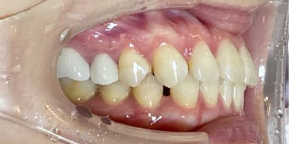

26歳女性のビフォーアフター

| 診断 | 空隙,叢生 |

| 治療方針 | 治療方針:前歯の咬合関係改善と空隙閉鎖を主な目的にて主にIPR(歯と歯の間をわずかに削合してスペースを獲得する方法)を組み込んだ動的矯正治療を行い、空隙、前歯咬合を改善後、保定を行う。臼歯部の咬合関係はプランの都合上維持することとした |

| 治療費 ※ | 69万8千円(診断、型取り、矯正中のメンテナンス、保定装置を含む料金) |

| 治療期間 | 1年8か月 |

| リスク | 1日20時間以上マウスピースを使用できない場合、歯が動かなかったり、想定しない誤差により不完全に終わる可能性がある。装着時や食事時に痛みを伴う。歯肉退縮や虫歯になるおそれがある。また、指導通りに装着できていない場合や適切なブラッシングが出来ていないとそのリスクが高くなる。歯根が短くなることがある。ごくまれに歯の神経が損傷してしまうことがある。過去にぶつけたり深い虫歯治療をしたことがあるとそのリスクはやや高くなる。矯正後には保定装置が必要。適切な使用ができない場合、後戻りの原因となる。将来的に歯並びが動いて再矯正が必要な場合がある。舌癖(舌で歯を押し出す癖)親知らずが正常に生えていない場合、その可能性がやや高くなる。 |